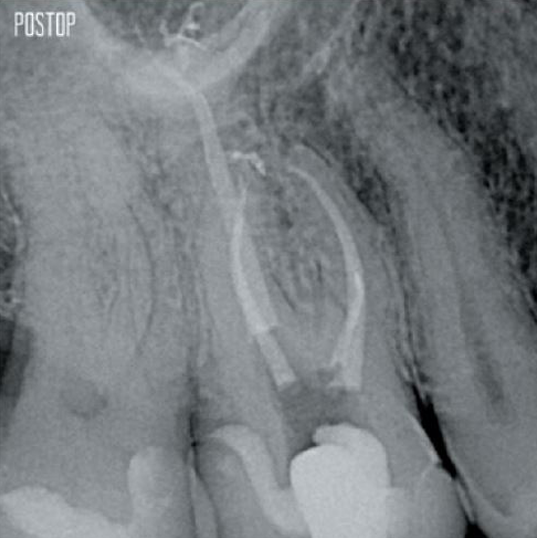

Fotos cortesía del Dr. Ahmed Salman

Más conservación de dentina. Se garantiza la conformación, irrigación y obturación adecuadas.